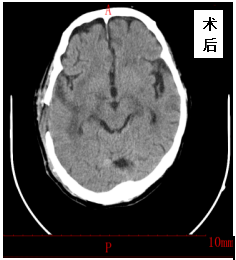

2021年03月04日,金洞乡桂花村村民张XX因突发高血压脑出血急诊来我院就诊,入院时患者意识障碍,左侧肢体偏瘫,急诊CT示:颅内大量出血,出血量约150ml,病情十分危重,患者随时会出现生命危险,需要紧急手术,内一科李太斌主任及时请外科杨继金副院长会诊,确定行急诊开颅血肿清除引流术,经以杨继金副院长为首的外科手术麻醉团队的共同努力,成功顺利的为该患者施行颅内血肿清除术,术后第二天患者神志逐渐恢复正常,左侧偏瘫肢体逐渐恢复正常,出院时,患者已经能自主站立行走,现已痊愈出院。